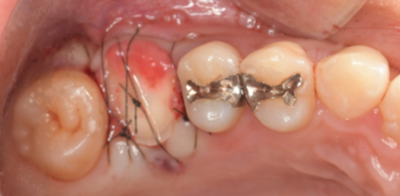

移植手術後

右上6抜歯1ヶ月後、移植手術を行った。

右下8を抜歯し右上6部に移植、縫合糸で固定した。

移植手術後、治癒に異常を認めなかったため、移植2週間後に根管治療を行った。